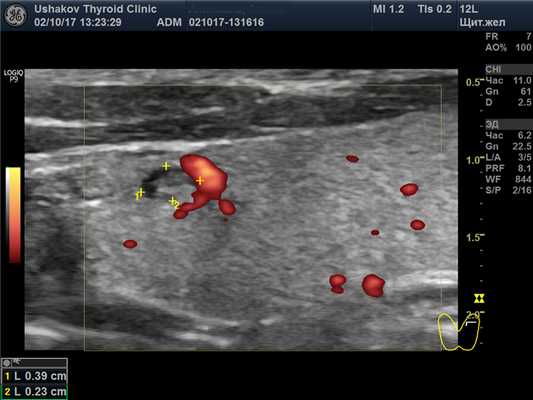

В правой доле щитовидной железы в центрально-каудальной части почти до её краев (в поперечной проекции) расположен овоидоподобной формы узел 22,9х20,7х33,1 мм (7,4 мл), окруженный по всему периметру чёткой гипоэхогенной границей-контуром, значительно неоднородный за счет множественных анэхогенных (жидкостных) участков (около 70% от объёма узла), преимущественно с чёткими границами в виде узких перегородок с изо- и гиперэхогенной (фиброзной) тканью и изоэхогенной тканью по периметру узла; при ЭДК заметно примыкание к узлу с кранио- и каудальной сторон магистральных сосудов, и умеренный кровоток по части периметра и мало интенсивный внутри узла (в перегородках); при эластографии SR 2,8 (3,3 - в обл. некоторых перегородок). Вне узла ткань изоэхогенная, почти однородная; в краниальном полюсе 21,2х15х15,1 мм (2,3 мл), а также медиально. В режиме ЦДК и ЭДК кровообращение в этой ткани в малой степени усилено.

Рис. 27.6. Пример 1. (правая доля, продольная проекция; ЭДК).

К узлу с краниальной и медиальной сторон подходят магистральные сосуды, создавая вокруг него, почти по всему периметру, умеренной интенсивности кровоток, с малой насыщенностью в тканевых перегородках узла.

Следует проследить источники сосудистой сети узла (в данном случае, она исходит из нескольких магистральных сосудов из ветвей верхней и нижней щитовидных артерий). Такая особенность важна, поскольку сообщает о закономерном поступлении к узлу нервных стимулов по нервным волокнам, сопровождающим сосуды.

Кровеносная сеть в узле также закономерна. Она соответствует биологически естественному распределению сосудов разных порядковых уровней в ткани узла, по мере формирования его сегментов. В данном случае мы наблюдаем явный окружной кровоток (рис. 27.6) и в межсегментарных участках (по краю внутриузловых сегментов ткань сохраняется дольше именно за счёт более полноценного обеспечения кровью (и меньшего напряжения)).